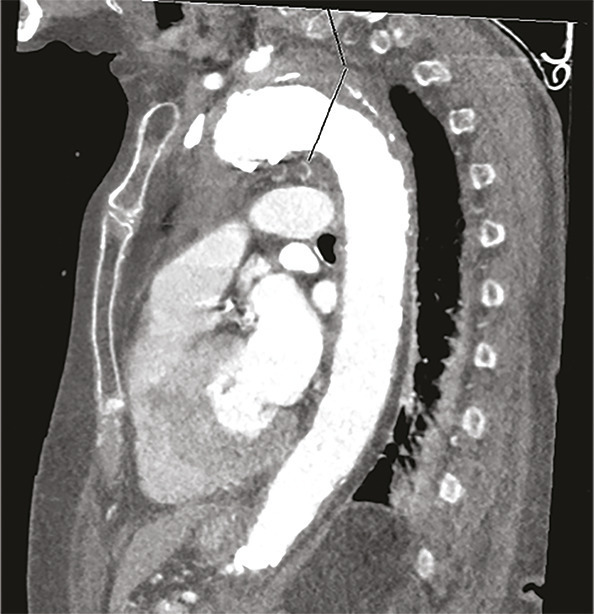

Cette femme de 95 ans arrivait aux urgences pour une douleur médiothoracique survenue brutalement quelques heures auparavant, transfixiante, sans irradiation ni facteur déclenchant évident. La patiente avait pour antécédents une hypertension artérielle (traitée par irbésartan et hydrochlorothiazide), une appendicectomie et une cholécystectomie. Devant une anisotension (différence de 30 mmHg de pression systolique [PAS] et 20 mmHg de diastolique entre les deux côtés), la patiente était placée en box de déchocage et monitoring continu. Un traitement par nicardipine au pousse-seringue électrique était instauré afin de contrôler cette hypertension majeure (221/114 mmHg), avec un objectif de PAS entre 150 et 170 mmHg. Le reste de l’examen clinique ne notait pas d’autres anomalies. Le bilan biologique montrait une élévation des D-dimères majeure (> 6 000 µg/L) et une insuffisance rénale. Malgré un débit de filtration glomérulaire (DFG) à 24 mL/min/m², la probabilité élevée d’une dissection aortique poussait à réaliser une tomodensitométrie thoraco-abdominopelvienne (fig. 1 et 2 ) avec injection de produit de contraste iodé, montrant un hématome intramural de la crosse de l’aorte. Après discussion pluridisciplinaire, l’indication chirurgicale était récusée du fait de l’âge avancé de la patiente et du risque opératoire.

Les syndromes aortiques aigus comprennent la dissection, l’ulcère et l’hématome intramural. Ce dernier, décrit pour la première fois en 1920,1 résulte d’une rupture des vasa vasorum sans déchirure intimale et est responsable de 10 à 40 % des syndromes aortiques aigus.2, 3 Le diagnostic se fait uniquement sur l’imagerie, généralement une tomodensitométrie thoracique injectée avec une augmentation d’épaisseur de la paroi aortique de plus de 5 mm.4 Néanmoins, il existe des facteurs clinico-biologiques d’orientation diagnostique comme l’asymétrie tensionnelle ou, selon certain auteurs, l’élévation des D-dimères.5 Selon sa localisation sur le trajet de l’aorte l’hématome est classé Stanford A ou B avec des taux de survie comparables aux dissections aortiques. Pouvant se résoudre de manière spontanée ou se rompre dans un tableau de dissection aortique, sa prise en charge fait débat. Ainsi, le traitement peut être médical avec contrôle tensionnel strict et surveillance monitorée des paramètres hémodynamique, ou chirurgical (mêmes indications que la dissection aortique). On peut également citer le traitement endo-aortique (pose d’une prothèse aortique synthétique par voie endoluminale) qui reste controversé en raison du risque d’endofuites secondaires, de pseudo-anévrismes ou de rupture intimale.6